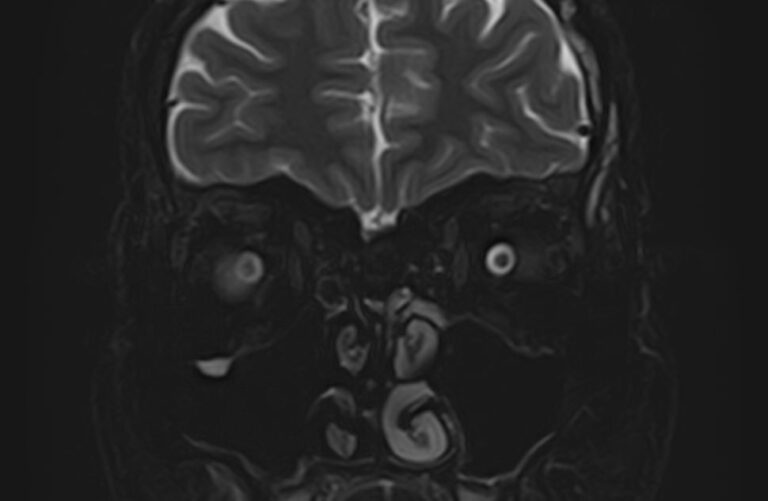

МРТ глазных орбит является современным способом диагностики патологии глазниц, в которых расположены глазные яблоки и их придатки (окружающая жировая клетчатка, зрительные нервы, слезные железы, мышцы глаза, связочный аппарат, кровеносные сосуды). МРТ орбит также позволяет получить детальную информацию о состоянии мягких тканей периорбитальных областей (тканей, окружающих глазницу).

Магнитно-резонансную томографию назначают при необходимости детального изучения мягкотканных структур глазниц. В результате исследования получают срезы анатомической области, на которых можно рассмотреть мельчайшие элементы. МРТ орбит обеспечивает визуализацию следующих структур:

• элементы глазного яблока, включая оболочки;

• периорбитальная клетчатка;

• мышечный аппарат;

• зрительный нерв;

• слезные железы.

Ангиорежим позволяет изучить сосуды глаза (глазная артерия и вены сетчатки).